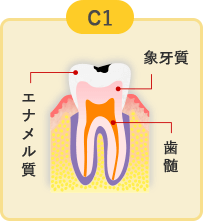

軽度のむし歯

歯の表面にあるエナメル質がむし歯に侵されています。